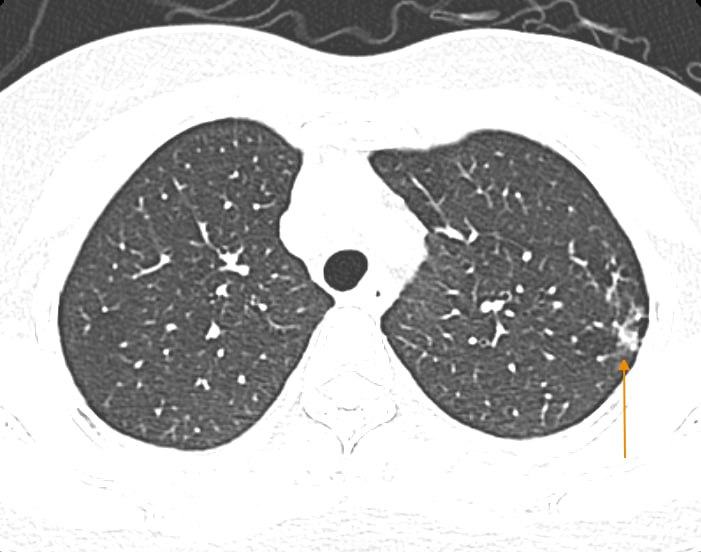

Tại Bệnh viện Đa khoa Medlatec, bệnh nhân được test có dương tính với cúm A. Hình ảnh chụp cắt lớp vi tính phổi độ phân giải cao cho thấy bệnh nhân gặp biến chứng viêm phổi. Hiện tại, bệnh nhân tiếp tục được điều trị và theo dõi tại khoa Nội.

Mắc cúm A, người phụ nữ Hà Nội phổi như bị bóp nghẹt, "không thể thở nổi"- Ảnh 1.

Hình ảnh chụp CT cho thấy tổn thương phổi của bệnh nhân H. (Ảnh: Bác sĩ cung cấp).